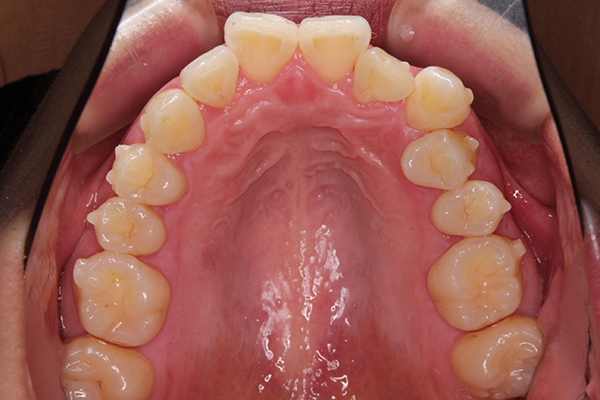

アタッチメントがついた写真が、こちら。

ぽつぽつと小さなものが並んでついていて

ちょっとかわいいです。笑